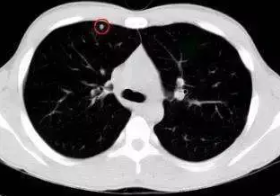

在体检中,许多人发现了肺部小结节。这个小小的肺部阴影正在引起恐慌。难道肺结节最终会发展成肺癌吗?错!体检报告中提到的结节实际上是影像学研究中常见的医学术语。只要是直径小于3厘米的肺部阴影,临床上就称为肺结节。小于1厘米的阴影是一个肺部小结节。